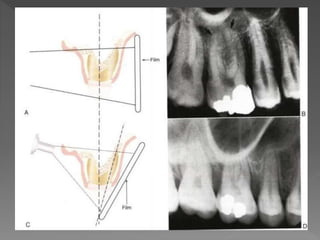

The document outlines general rules for dental X-ray exposure, including explaining the procedure to the patient, positioning the patient correctly, adjusting exposure factors, ensuring the film is parallel to the tooth, and taking precautions like using lead shields. Key steps are positioning the patient, setting exposure factors to get the right angle and focus, placing the film properly, and processing it safely after capturing the image.